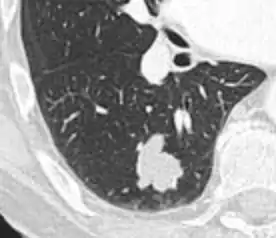

subpleural nodule.[9]

Round well-delineated solid lung nodule with smooth border.[9]

Lobulated nodule.[9]

Spiculated lung nodule.[9]

A "notch sign".[9]

A triangular perifissural node can be diagnosed as a benign lymph node.[9]